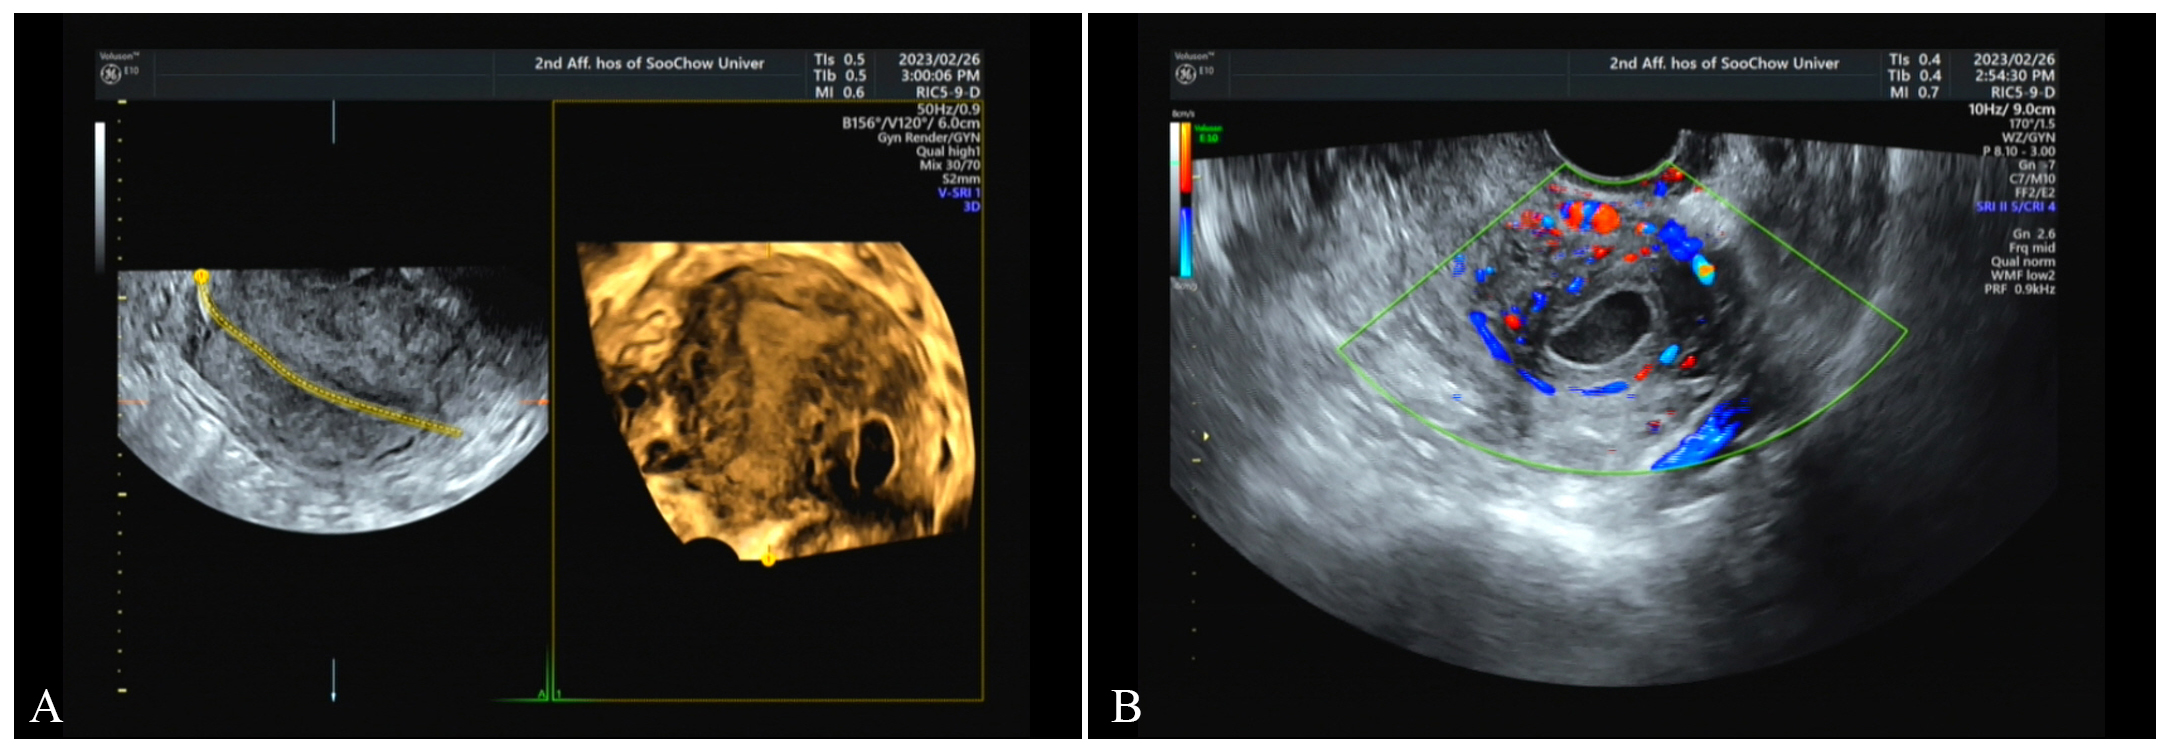

Fig. 1.

On February 26, transvaginal ultrasound scan. (A) A gestational sac

was seen near the uterine angle, measuring approximately 21 mm

On February 28, transvaginal three-dimensional ultrasound (TDU). (A) There was an echo of the gestational sac between the muscle walls. (B) Blood flow signals around it are increased.

TDU enables comprehensive scanning of the uterus in sagittal, coronal, and other planes, facilitating the determination of whether the gestational sac communicates with the fallopian tubes or uterine cavity, thereby accurately identifying the location of an ectopic pregnancy. Conventional transvaginal ultrasound can provide information on the longitudinal and transverse sections of the uterus but fails to precisely distinguish the relationships between the uterine cavity, uterine horns, and interstitial regions in the coronal plane, which may lead to misdiagnosis as a cornual or interstitial pregnancy [7]. In this case, our initial transvaginal ultrasound incorrectly diagnosed the patient with uterine horn pregnancy.

Furthermore, TDU can accurately visualize the position and size of the

gestational sac within the myometrium, its relationship with the uterine cavity,

and the distance from the uterine serosal layer. This allows for differentiation